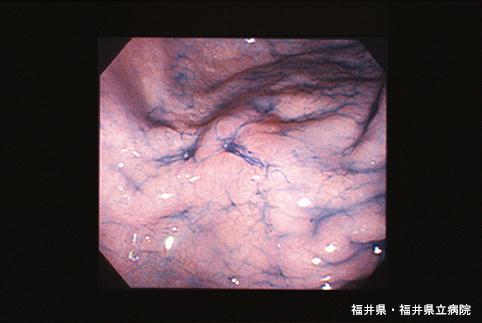

症例提示(所在地,施設名等): 福井県・ 福井県立病院 (Dr.細川)

インジゴカルミンを撒布すると頂部の陥凹と大彎側に斜め肛門側に向かう溝が明瞭となり、隆起を覆う粘膜はわずかに発赤しているものの周囲と同様の小区像です。 中央の陥凹からの生検でGroup V,印鑑細胞癌が得られました。

疾患(病理主体)の分類悪性上皮性腫瘍/印環細胞癌

部位(臓器別)胃(部位)/体部

腫瘍の肉眼分類3型(潰瘍浸潤型)/

病変の最大径(ミリ)10〜14

腫瘍の深達度mp